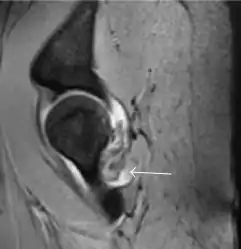

Most of the angles and measurements described in the plain radiograph section can be accurately reproduced on MRI. In addition, the superiority of MRI resolution with intra-articular contrast allows detection of labral and chondral abnormalities that may influence the choice of medical, percutaneous, or surgical management (Figure 9).[1]

Figure 9:

Sagittal T1 weighted image showing anterosuperior labral tear.[1]

Sagittal T1 weighted image showing chondral lesion.[1]

Sagittal CT-arthrography showing posteroinferior chondral injury.[1]

Coronal CT-arthrography (d) showing ligamentum teres tear.[1]

MR arthrography has proven superior in accuracy when compared to native MR imaging. It is considered the best technique to assess the labrum. Knowledge of the normal variable morphology of the labrum helps to differentiate tears from normal variants. A triangular shape is most commonly seen in 66% of asymptomatic volunteers, but round, flattened, and absent labra can also be found in asymptomatic populations. MR arthrography has demonstrated sensitivity over 90% and specificity close to 100% in detecting labral tears. Loose bodies are demonstrated as filling defects surrounded by the hyperintense gadolinium.[1]

Association between labral tears and chondral damage has been demonstrated. This underscores the interaction between cartilage and labrum damage in the progression of osteoarthritis. Chondral damage to the posteroinferior part of the acetabulum as a contrecoup lesion occurs in approximately one-third of pincer cases secondary to persistent abutment on the anterior part of the joint leading to a slight posteroinferior subluxation. This is considered a bad prognosis sign.[1]

MR arthrography can also demonstrate ligamentum teres rupture or capsular laxity, which are debated causes of microinstability of the hip. Elongation of the capsule or injury to the iliofemoral ligament or labrum may be secondary to microtrauma in athletes. MR can demonstrate abnormalities in these cases, such as increased joint volume or a ligamentum teres tear (Figure 9).[1]